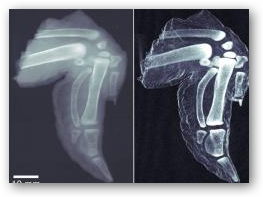

A set of simple silicon filters could dramatically improve the quality of X-ray images produced in hospitals and at airport checkpoints. The team adapted a technique known as dark-field microscopy, which is normally used by biologists to get a clearer view of cells under a light microscope.

The technique provides a more detailed picture of fractured bone and could help airport security scanners distinguish plastic explosives from harmless substances. Although the process means exposing the subject to a higher total dose of radiation, Pfeiffer says this can be justified in some circumstances.

X-ray images normally reveal the way different materials, including body tissue, absorb X-ray radiation. Strongly absorbing areas are white and weakly absorbing ones black. But finer details are often lost in a fog caused by areas with intermediate radiation-absorbing ability. The technique is not yet ready for deployment in hospitals as it only works with relatively low-intensity X-rays.